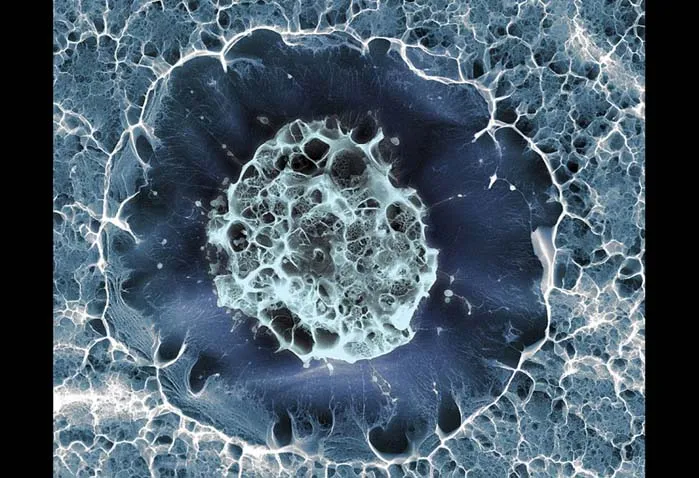

سلول بنیادین انسان

این تصویر با تصویربرداری ریزنگاری الکترونی از سلول بنیادی در مغز استخوان گرفته شده است. سلولهای بنیادی تقسیم میشوند و انواع دیگری از سلولهای بدن را میسازند.

قطر این سلول حدودا ۱۵ میکرومتر (۰٫۰۱۵ میلیمتر) است و قبل از تصویربرداری آن را در دمای منفی ۱۵۰ درجهی سانتیگراد یخ کردند.